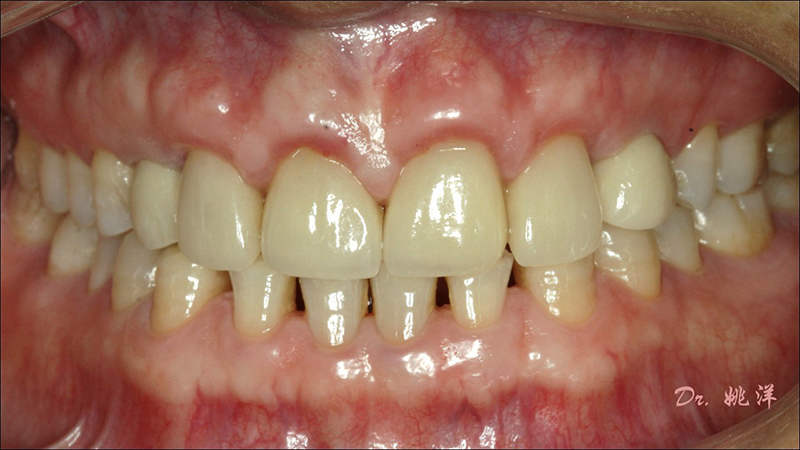

導(dǎo)航下精細(xì)分配修復(fù)間隙,精細(xì)規(guī)劃植入方向,避開(kāi)上頜竇底,精確植入

從術(shù)后CBCT顯示可以看出,手術(shù)操作中完美地避開(kāi)上頜竇底,并兼顧了正確的種植方向和修復(fù)間隙

種植后數(shù)字化取模,前牙美學(xué)間隙精確分配

從最終修復(fù)效果可以看出:23,24間隙不足修復(fù)兩顆,修復(fù)為1顆牙。因?yàn)榻?jīng)過(guò)數(shù)字化設(shè)計(jì)和精確導(dǎo)航植入,修復(fù)體齦緣協(xié)調(diào)自然